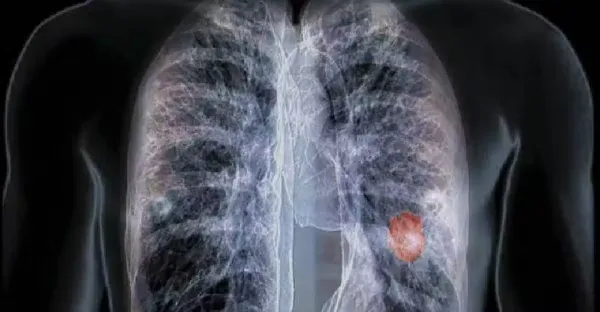

不抽菸不喝酒!45歲女確診「晚期肺癌」只因長期在做兩件事 5類高危人群要重視「早期癥狀」